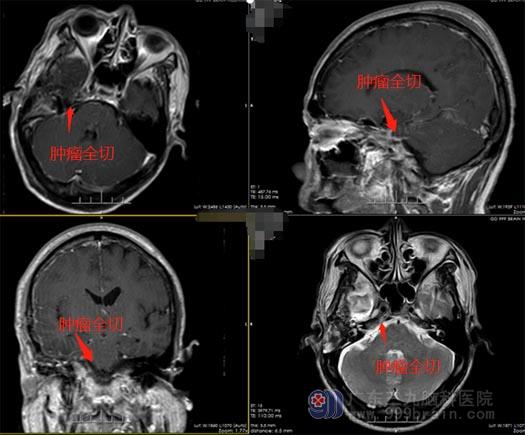

明确周大叔无明显手术禁忌症,由鲁明主刀,在全麻下行“右侧海绵窦脑膜瘤切除术”,手术全切肿瘤。术后周大叔恢复正常,无神经系统的损伤,已康复出院。